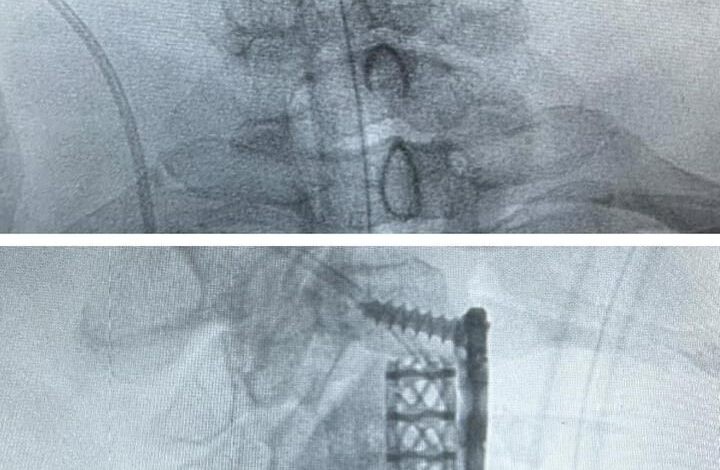

وبعد إجراء الفحوصات الطبية اللازمة تبيّن وجود ضغط على الحبل الشوكي بسبب الغضاريف بين الفقرات الثالثة والرابعة العنقية، ونتوءات عظمية خلف الفقرة العنقية الرابعة، حيث قام الفريق الطبي بقيادة إستشاري جراحة العظام وجراحة العمودي الفقري د. متعب أبو راس بإزالة الغضروف مع استئصال جزئي للفقرة الرابعة؛ لتحرير الحبل الشوكي، ليتم بعدها تثبيت الفقرات بنجاح، حيث تحسنت حالة المريض تماماً بعد العملية الجراحية -ولله الحمد-.

يذكر أن هذه العملية تعد الأولى من نوعها في مستشفى الملك سلمان، كما أنه يجري مختلف العمليات الجراحية الدقيقة والنوعية؛ بتطبيق أفضل معايير الجودة والتميز الصحي عبر تقنيات مستحدثة ووجود كوادر متخصصة.